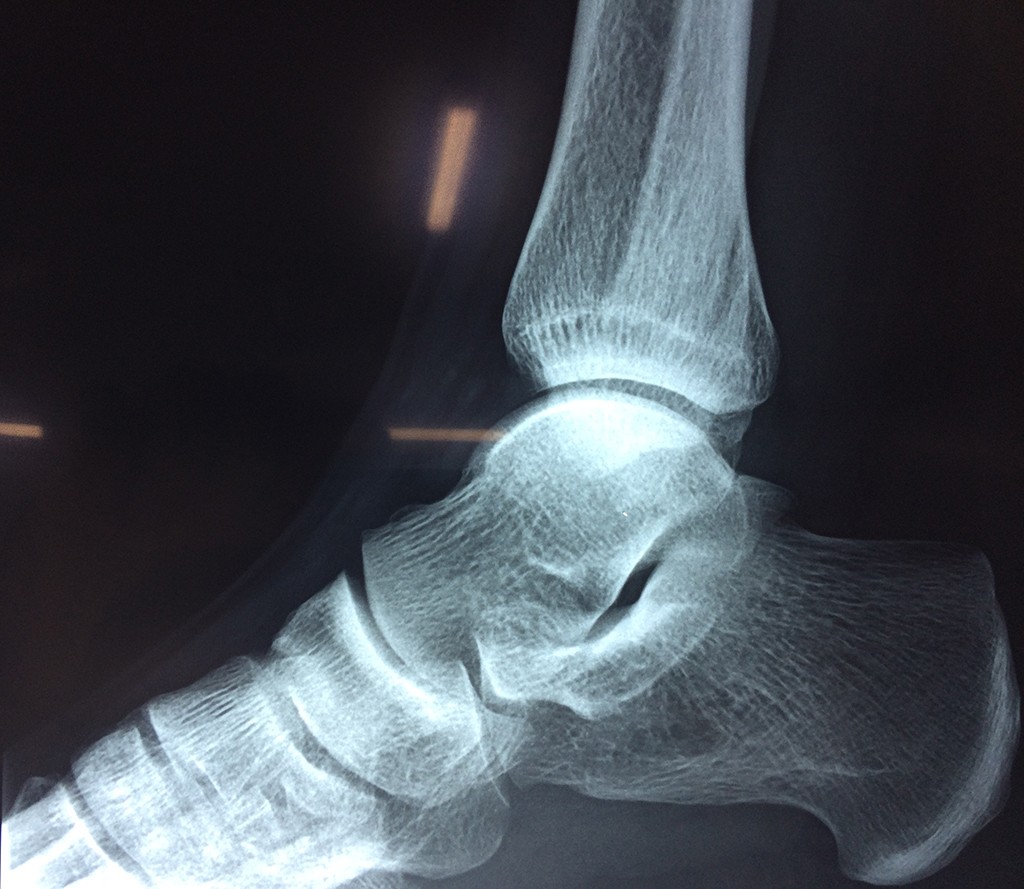

Una fractura de tobillo es la rotura de uno o más de los huesos del tobillo. Estas fracturas pueden ser:

- Parciales (el hueso está sólo parcialmente fisurado, no del todo).

- Completas (el hueso está perforado y está en 2 partes).

Algunas fracturas de tobillo pueden requerir cirugía si:

- Los extremos de los huesos están desalineados entre sí (desplazados).

- La fractura se extiende hasta la articulación del tobillo (fractura intra-articular).